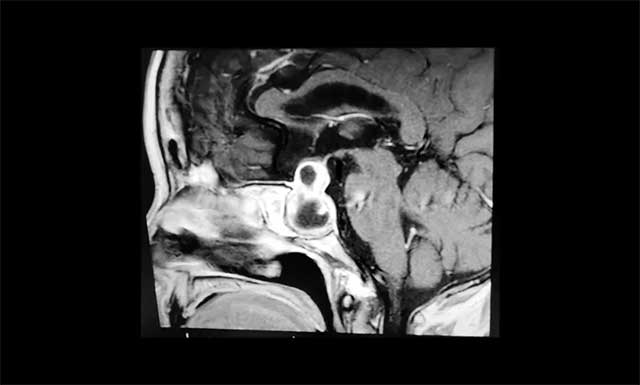

鞍区MRI平扫+增强显示:蝶鞍显著扩大,鞍区见不规则囊实样肿块,大小约2.6*2.1*3cm,视交叉上抬,鞍上池受压,侵及双侧海绵窦,蝶窦结构紊乱,临近鞍底下陷、部分骨壁缺失。

▲ 肿瘤向鞍内、鞍上、鞍旁发展,呈“哑铃形”

李士其教授分析:肿瘤主体位于鞍内、鞍上、鞍旁发展,呈“哑铃”形。从影像学资料上看,发现瘤体已经非常大了,属于巨大垂体瘤。瘤体占据鞍区,并向蝶窦和鞍上发展,侵袭双侧海绵窦,视神经、视交叉受压,所以需要马上进行手术切除,解除压迫。若任其发展,将来有失明的风险。